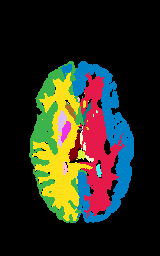

Segmentation of brain magnetic resonance images (MRI) is crucial for the analysis of the human brain and diagnosis of various brain disorders. The drawbacks of time-consuming and error-prone manual delineation procedures are aimed to be alleviated by atlas-based and supervised machine learning methods where the former methods are computationally intense and the latter methods lack a sufficiently large number of labeled data. With this motivation, we propose CORPS, a semi-supervised segmentation framework built upon a novel atlas-based pseudo-labeling method and a 3D deep convolutional neural network (DCNN) for 3D brain MRI segmentation. In this work, we propose to generate expert-level pseudo-labels for unlabeled set of images in an order based on a local intensity-based similarity score to existing labeled set of images and using a novel atlas-based label fusion method. Then, we propose to train a 3D DCNN on the combination of expert and pseudo labeled images for binary segmentation of each anatomical structure. The binary segmentation approach is proposed to avoid the poor performance of multi-class segmentation methods on limited and imbalanced data. This also allows to employ a lightweight and efficient 3D DCNN in terms of the number of filters and reserve memory resources for training the binary networks on full-scale and full-resolution 3D MRI volumes instead of 2D/3D patches or 2D slices. Thus, the proposed framework can encapsulate the spatial contiguity in each dimension and enhance context-awareness. The experimental results demonstrate the superiority of the proposed framework over the baseline method both qualitatively and quantitatively without additional labeling cost for manual labeling.